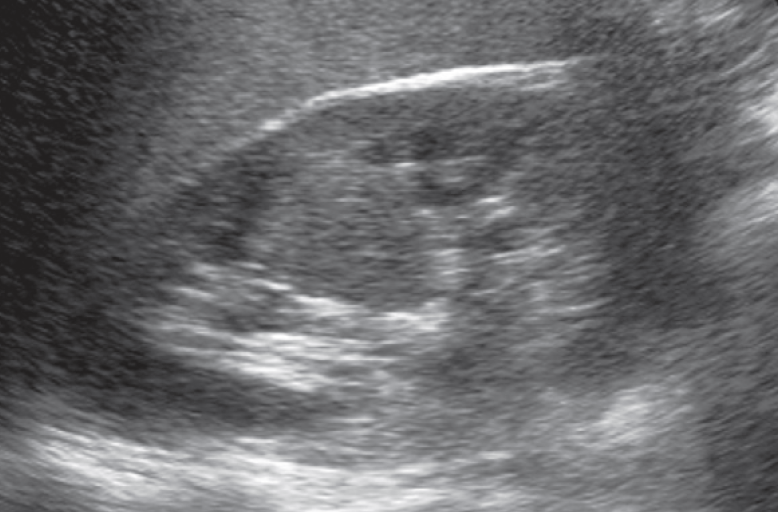

2-Kidney hump

تسمى أيضا Dromedary hump وهي مثل البروز في شكل parenchyma الكلية كسنام الجمل. سماكتها يجب أن تتناسق مع بقية parenchyma المحيطة بدون بروز. هي شائعة تحديدا في الكلية اليسرى وذلك لأن التغير يحدث في مرحلة تطور الجنين وضغط الطحال على الكلية.

في هذه الحالات يجب التأكد من السماكة (متناسقة) و echogenicity (غير مختلفة) و colour Doppler (طبيعية).